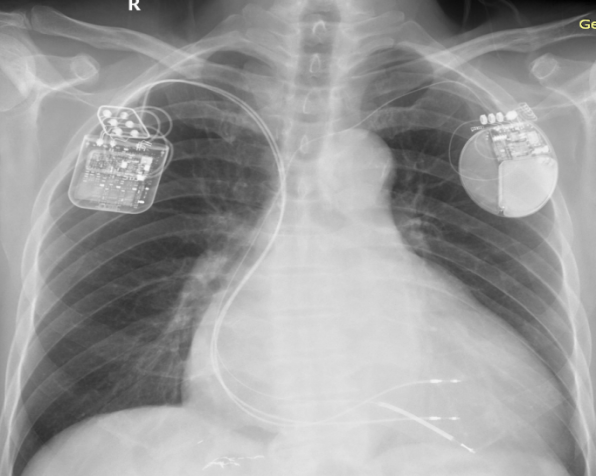

CCM+ICD术后X片——正位及左前斜位

3、CCM联合ICD一站式手术的难点:精准的放置三根导线对此次手术尤为关键,也是手术的难点,不仅要求导线参数满足要求,还需要兼顾三根导线放置的位置和间距。首先是准备静脉通路,在右侧锁骨下静脉穿刺,送入导丝,在透视下确认钢丝成功进入右心系统;之后进行囊袋制作;随后进行起搏导线植入,两根起搏导线之间的距离在2cm以上,ICD导线与普通导线距离3cm以上(ICD导线除颤线圈长度,可作为导线之间距离的参考),从而保证CCM的正常感知与发送且不会互相干扰,最终所有电极导线都被精准完成植入,分别测试三根电极导线的起搏阈值和起搏阻抗并记录。连接导线与脉冲发生器,设定输出为7.5V。联合测试,三根电极均可以正常工作且彼此无干扰。同时考虑到除颤的效果,将ICD放置在左侧,CCM放置在右侧。此患者术后心电图对比,完美展示了自身心律与起搏心率下CCM正常工作。